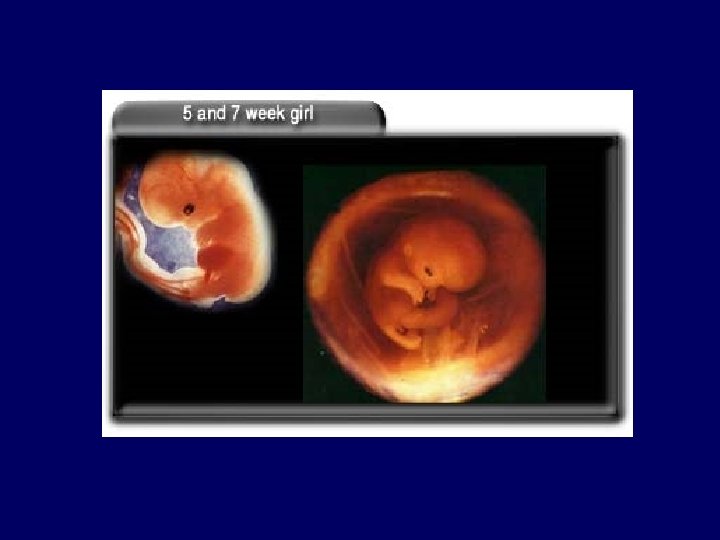

Embryonic period • Period of organogenesis: 2 -8 weeks • Time of greatest susceptibility to teratogens • Critical stages for malformations of different organ systems during this period: – Neural tube closes by day 30 – Limb buds develop – Heart